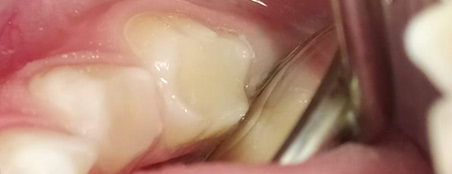

Эстетические реставрации. Дошколятам нравятся цветные пломбы, а детям постарше врач поставит пломбу, точь-в-точь совпадающую по цвету, форме и рельефу с натуральным зубом.

Коронки. Устанавливаем коронки на молочные зубы, защищая их от дальнейшего разрушения и ранней потери. Недорогие металлические для жевательный зубов и белые циркониевые в зоне улыбки.

Но иногда пломбирования – недостаточно. Сломанные молочные зубы, рано утраченные или зубы после неоднократных перелечиваний требуют помощи стоматолога-ортопеда.

Несъемное протезирование. На проблемный зуб можно поставить коронку, которая перераспределит нагрузку, позволит полноценно ребенку жевать и разговаривать, а также сохранит зуб от дальнейшего разрушения. Коронки делают из металла либо пластмассы. Пластмассовые коронки выглядят естественно, недороги, но не очень прочны, иногда нуждаются в замене. Металлические долговечны, но их изготовление требует от маленького пациента большей усидчивости и терпения.